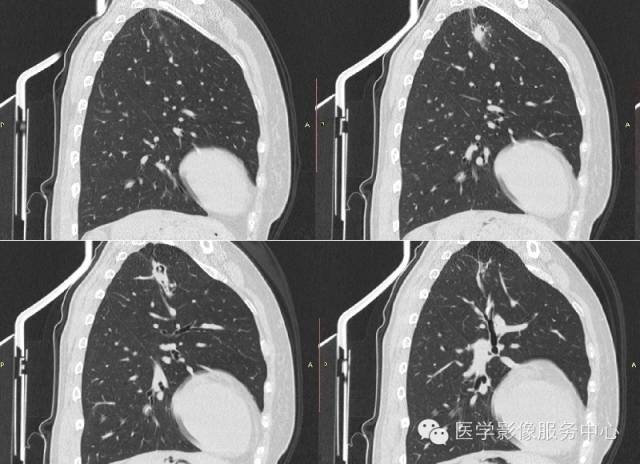

病史:

女,42岁,间断性咯血一年。

3、曲菌球:一般寄生在肺部慢性疾病所致的空洞或空腔内,常见的有结核空洞、支气管扩张、先天性肺囊肿等。空洞大小不等、洞壁薄厚不一,其内曲菌球一般呈圆形或卵圆形,密度均匀,边界光整,在洞内处于游离状态,可随体位改变而移动,曲菌球与洞壁之问形成一新月形的含气腔隙。曲菌球具有特征性的诊断价值。